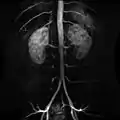

Additional images